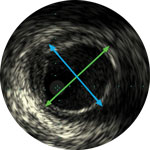

Lumen

Eccentric fibrotic plaque with deep calcium nodule

Acoustic shadowing

Vessel size: 5.5 mm diameter Plaque morphology: Fibrotic plaque with intimal and medial calcium Plaque geometry: Eccentric lesion Guidewire position: True lumen

Quick-Cross catheter: Confidently cross challenging morphologies Phoenix deflecting atherectomy: Front facing to cut, capture and clear mixed morphologies, including calcium; deflecting capabilities for larger luminal gain AngioSculpt scoring balloon: Score calcium to reduce dissection4 Stellarex DCB: Designed for performance in calcium